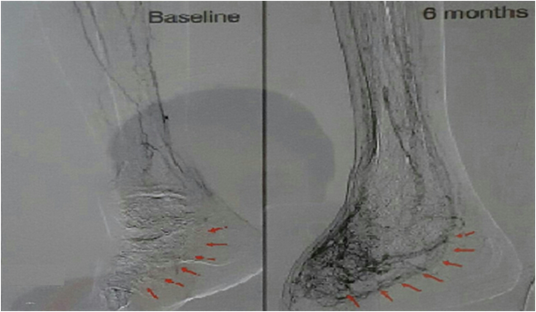

DIABETIC FOOT ULCERS

Stem cells are able to rapidly REGENERATE (re-grow and expand) new arterial/blood networks to facilitate the recovery of diabetic ischemia wounds.

Arrow in (baseline) indicates that there is no blood flow below the ankle at Baseline.

Arrow in (6 months) indicates the newly visible collateral vessels below the ankle at 6 months after treatment.